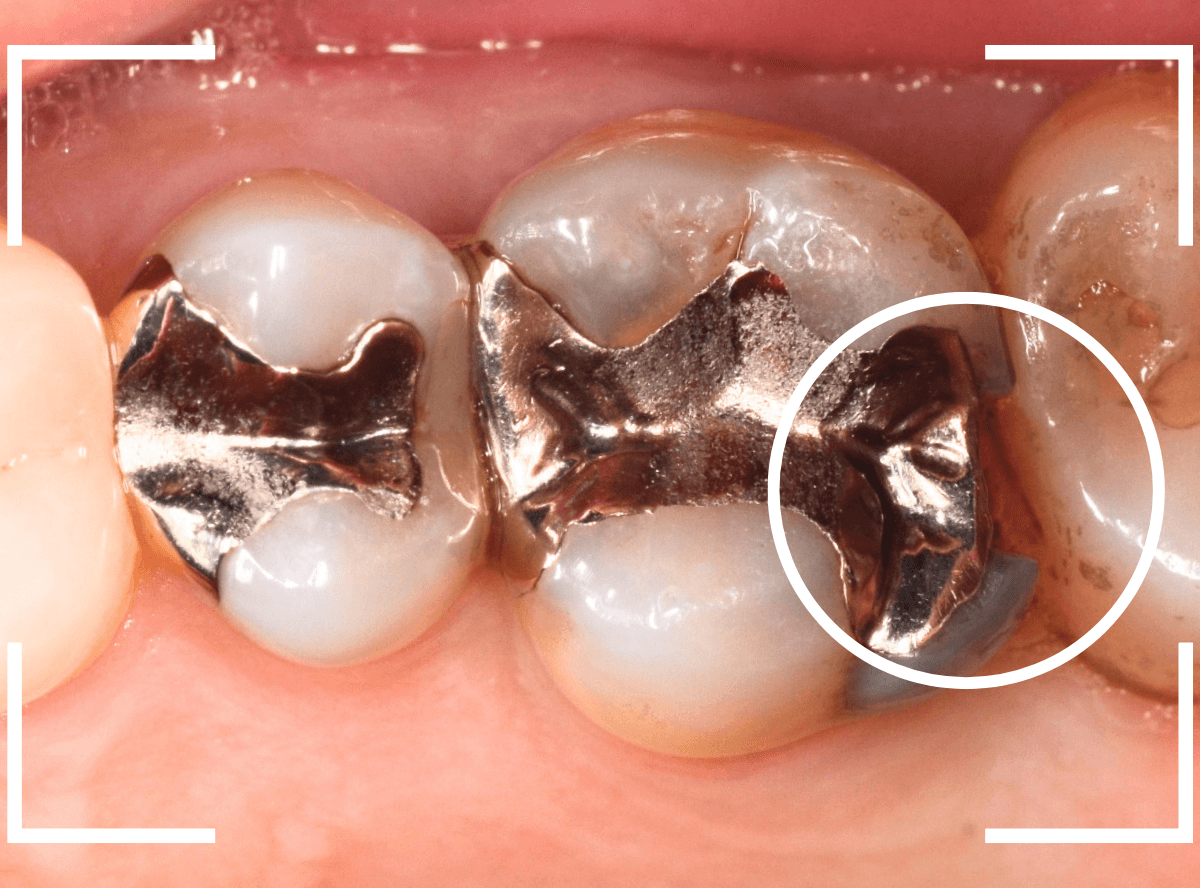

Case.17 虫歯治療後、オール・ジルコニア・クラウンとE-MAXで修復

今回は、奥歯が神経に達する虫歯になってしまった患者さんのケースです。

隣りの歯とのすき間に大きな穴が空いているのが見えます。

レントゲン写真で確認します。

金属のつめものの下が、神経まで達する大きな虫歯になっています。

手前の歯の虫歯も金属の中まで虫歯になっていました。

手前の歯の虫歯もかなり広い虫歯でした。